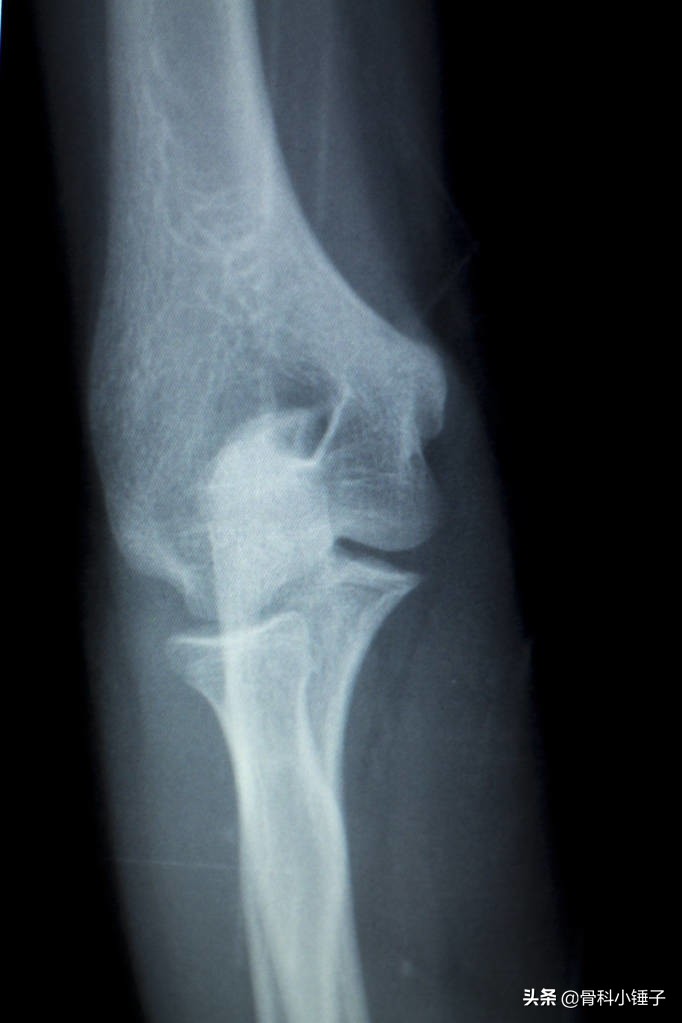

“网球肘”医学上称为“肱骨外上髁炎”。手臂负责伸肘的肌肉长期反复强烈的使用,不断收缩、牵拉,会使这些肌腱的附着处发生不同程度的急性或慢性积累性损伤,肌纤维产生撕裂、出血、机化、粘连,形成无菌性炎症反应。